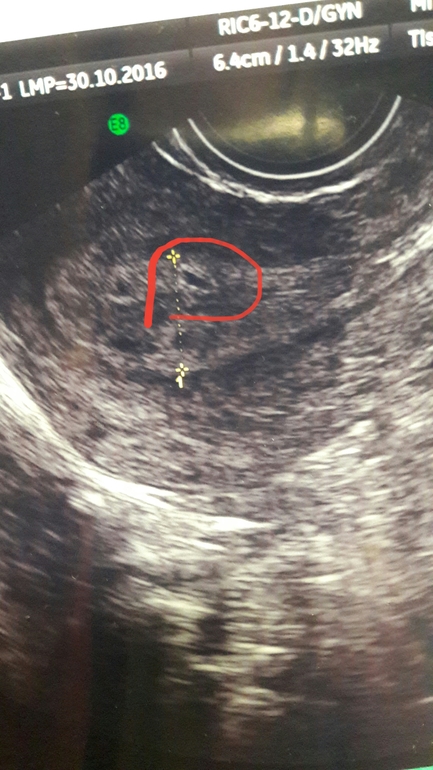

так не хочется во все это верить .И я почему то думаю что это оно , хоть я и не узист

Я так не думаю,просто в выходной экстренной пришлось ехать хотя-бы в эту платную.Всё ей было не видно ,кулачки под поясницу подкладывай , потом подушку и снова кулачки

не переживайте раньше времени,весь ее диагноз странный. Сделайте еще узи. все будет хорошо!

Позвонила врач сказала результат ХГЧ 35 и говорит отнеситесь к этому как к ложной беременности .Теперь я точно ничего не понимаю

Сдайте хгч, если прям тёмная мазня коричневая,потом с примесью крови,к сожалению внематочная (( у меня так было. У меня на узи в 4 нед 3 дня в матке не нашли..пришла с коричневой мазней еле нашла в ампулярном отделе. Быдо 4 нед и 6 дней.Вам желаю здоровой Б.

Не хочу вас пугать, но у меня с точно такими же симптомами и узи была внематочная в итоге. Но все может быть и хорошо) Лучше не думайте об этом, сдавайте анализы и через время на узи.

Однозначно надо смотреть на рост хгч. Узи через недельку повторить.

Тесты положительные или может сдавали хгч ? Рано для УЗИ ещё конечно , плотное яйцо увидят только через неделю не раньше